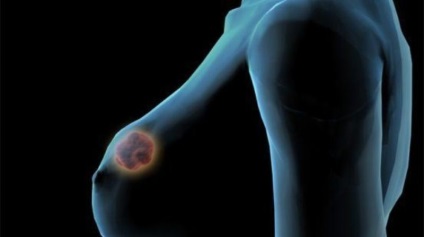

Fibroadenomatosis cancer de san: ce este? Așa a numit-o stare patologică în care glandei mamare apar mai multe tumori benigne compuse din țesuturi conjunctive și glandulare. Mastopatie fibroadenomatosis caracterizat printr-o tumoare având caracteristici specifice, care apar deja la examinarea inițială. Neoplasmele nu sunt capabile de dispariție spontane și deplasare. Tratamentul bolii este aproape întotdeauna efectuată pe cale chirurgicală. Tumora poate fi o lungă perioadă de timp pentru a rămâne în stare primară, nu creșterea în dimensiune. În cazul în care adenom constau în principal în țesutul glandular în fibrele conjunctive sunt fibroadenomas.

Unii medici cred fibroadenomatosis o formă de mastită, în curs de dezvoltare pe fondul tulburărilor hormonale. Tabloul clinic al bolii nu depinde de faza ciclului menstrual. Viteza de dezvoltare a tumorii pot fi diferite. Uneori nu depășește mărimea unui bob de mazare, iar în această stare rămâne de ani de zile. În unele cazuri, cu toate acestea, creșterea rapidă a tumorii poate duce la deformarea sânului. Uneori aceste modificări pot fi observate cu ochiul liber.